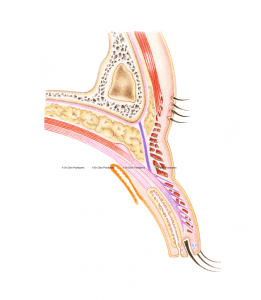

The most commonly performed eyelid surgery in people from East Asia is sometimes referred to as “double eyelid surgery”, and is a cosmetic surgical method that reconstructs the skin of the upper eyelid. Often oculoplastic surgeons also partially remove any skin surplus, which is a natural consequence of ageing. We oculoplastic surgeons can also create an eyelid crease – something that is naturally missing in people from East Asia (which is sometimes referred to as a “mono-lid”).

It is important that the doctor performing this procedure has special expertise in this area. Oculoplastic surgeons are ophthalmologists who specialize in eyelid surgery and who – like no other – understand the complex relationship between the eye and the eyelid. For example, an assessment of the different aspects of the eyelid such as eyelid height (the position of the lash line relative to the pupil), the amount of skin, the presence or absence of a so-called eyelid crease (the line above which the skin fold forms), the shape of the epicanthal fold, and the position and shape of the eyebrow should all be made preoperatively. It is also important to look for signs of dry (or wet) eyes, as this helps to prevent eye complaints after the procedure.